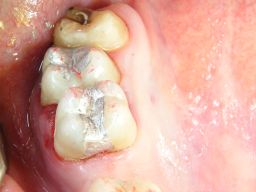

Warum ist das wichtig? Nun, Amalgam ist nicht gleich Amalgam. Es gibt, wie auch bei Composites, gravierende Qualitätsunterschiede schon im Material, die voll auf die Haltbarkeit der Füllungen durchschlagen. In einer Meta-Analyse haben sich Gamma-2-freie Amalgame mit Zink als besonders haltbar gezeigt - nach 13 Jahren waren noch 85 von 100 Füllungen im Mund. "Epoque 70" ist solch ein Amalgam und enthält darüberhinaus 70% Silber im Metallpulver. Dadurch bleibt es auch langfristig silbrig-hell, die Füllungen werden nicht schwarz. Die Bilder sind anklickbar! | ||||||||||||||||||||||||||||||||||||||||||||||||||||||||||||||||||||||||

![]() | Die Füllungen links wären auch in Composite gut vertretbar gewesen, die Füllungen rechts halten in Amalgam sicher länger als in Composite. Diese Amalgamfüllungen sind alle im Oberkiefer und im Alltag nicht sichtbar. |